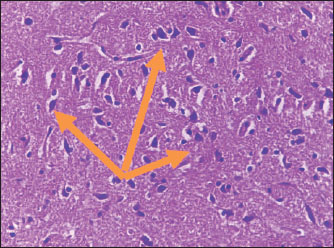

Brain of control group appeared normal structure of tissue with manifestation of Purkenji cells (Fig. 1), whereas sodium benzoate administration at low dose (200 mg/kg) occurred several histological lesions as hypertrophy of neurons (Fig. 2), pair nuclei arranged encompassed with clear space (Fig. 3), bleeding with degeneration of nerve cells (Figs. 4 and 5), respectively. In addition, lesions such as vacuolation, congestion, and accumulation of inflammatory cells were also evident (Figs. 6 and 7). However, severe histopathological lesions were observed following high-dose of sodium benzoate exposure, such as degeneration of neurons stained in dark blue (Fig. 8), prominent vascular duct with inflammation (Fig. 9), vacuolation, edema, and clear congestion as seen in Figures 1012, respectively.

Fig. 2. Points to the brain of sodium benzoate group (200 mg/kg): hypertrophy of neurons (H&E) (100×).

Fig. 3. Points to the brain of sodium benzoate group (200 mg/kg): pair of nuclei ranking enclitic by clear area (H&E) (100×).